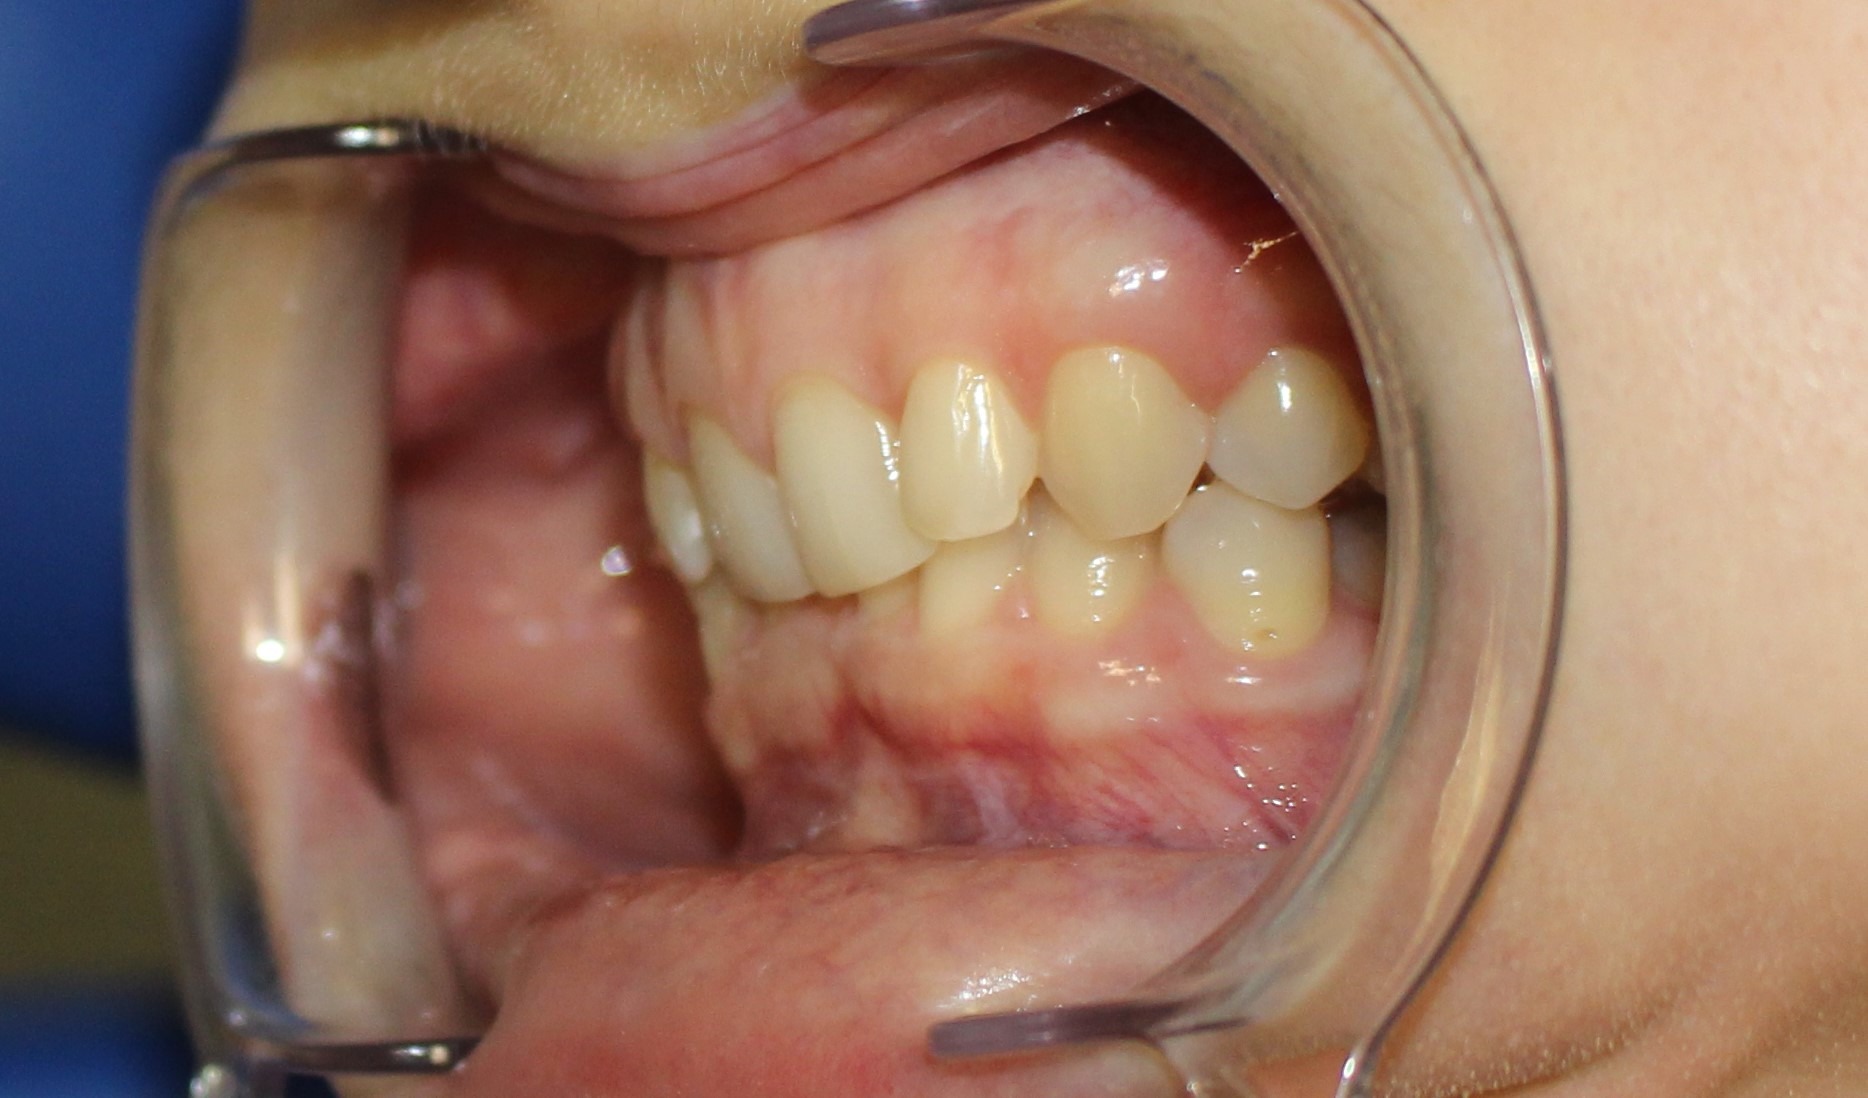

До

Дистальный глубокий прикус с ретрузией резцов верхней челюсти, тесное положение резцов нижней челюсти.